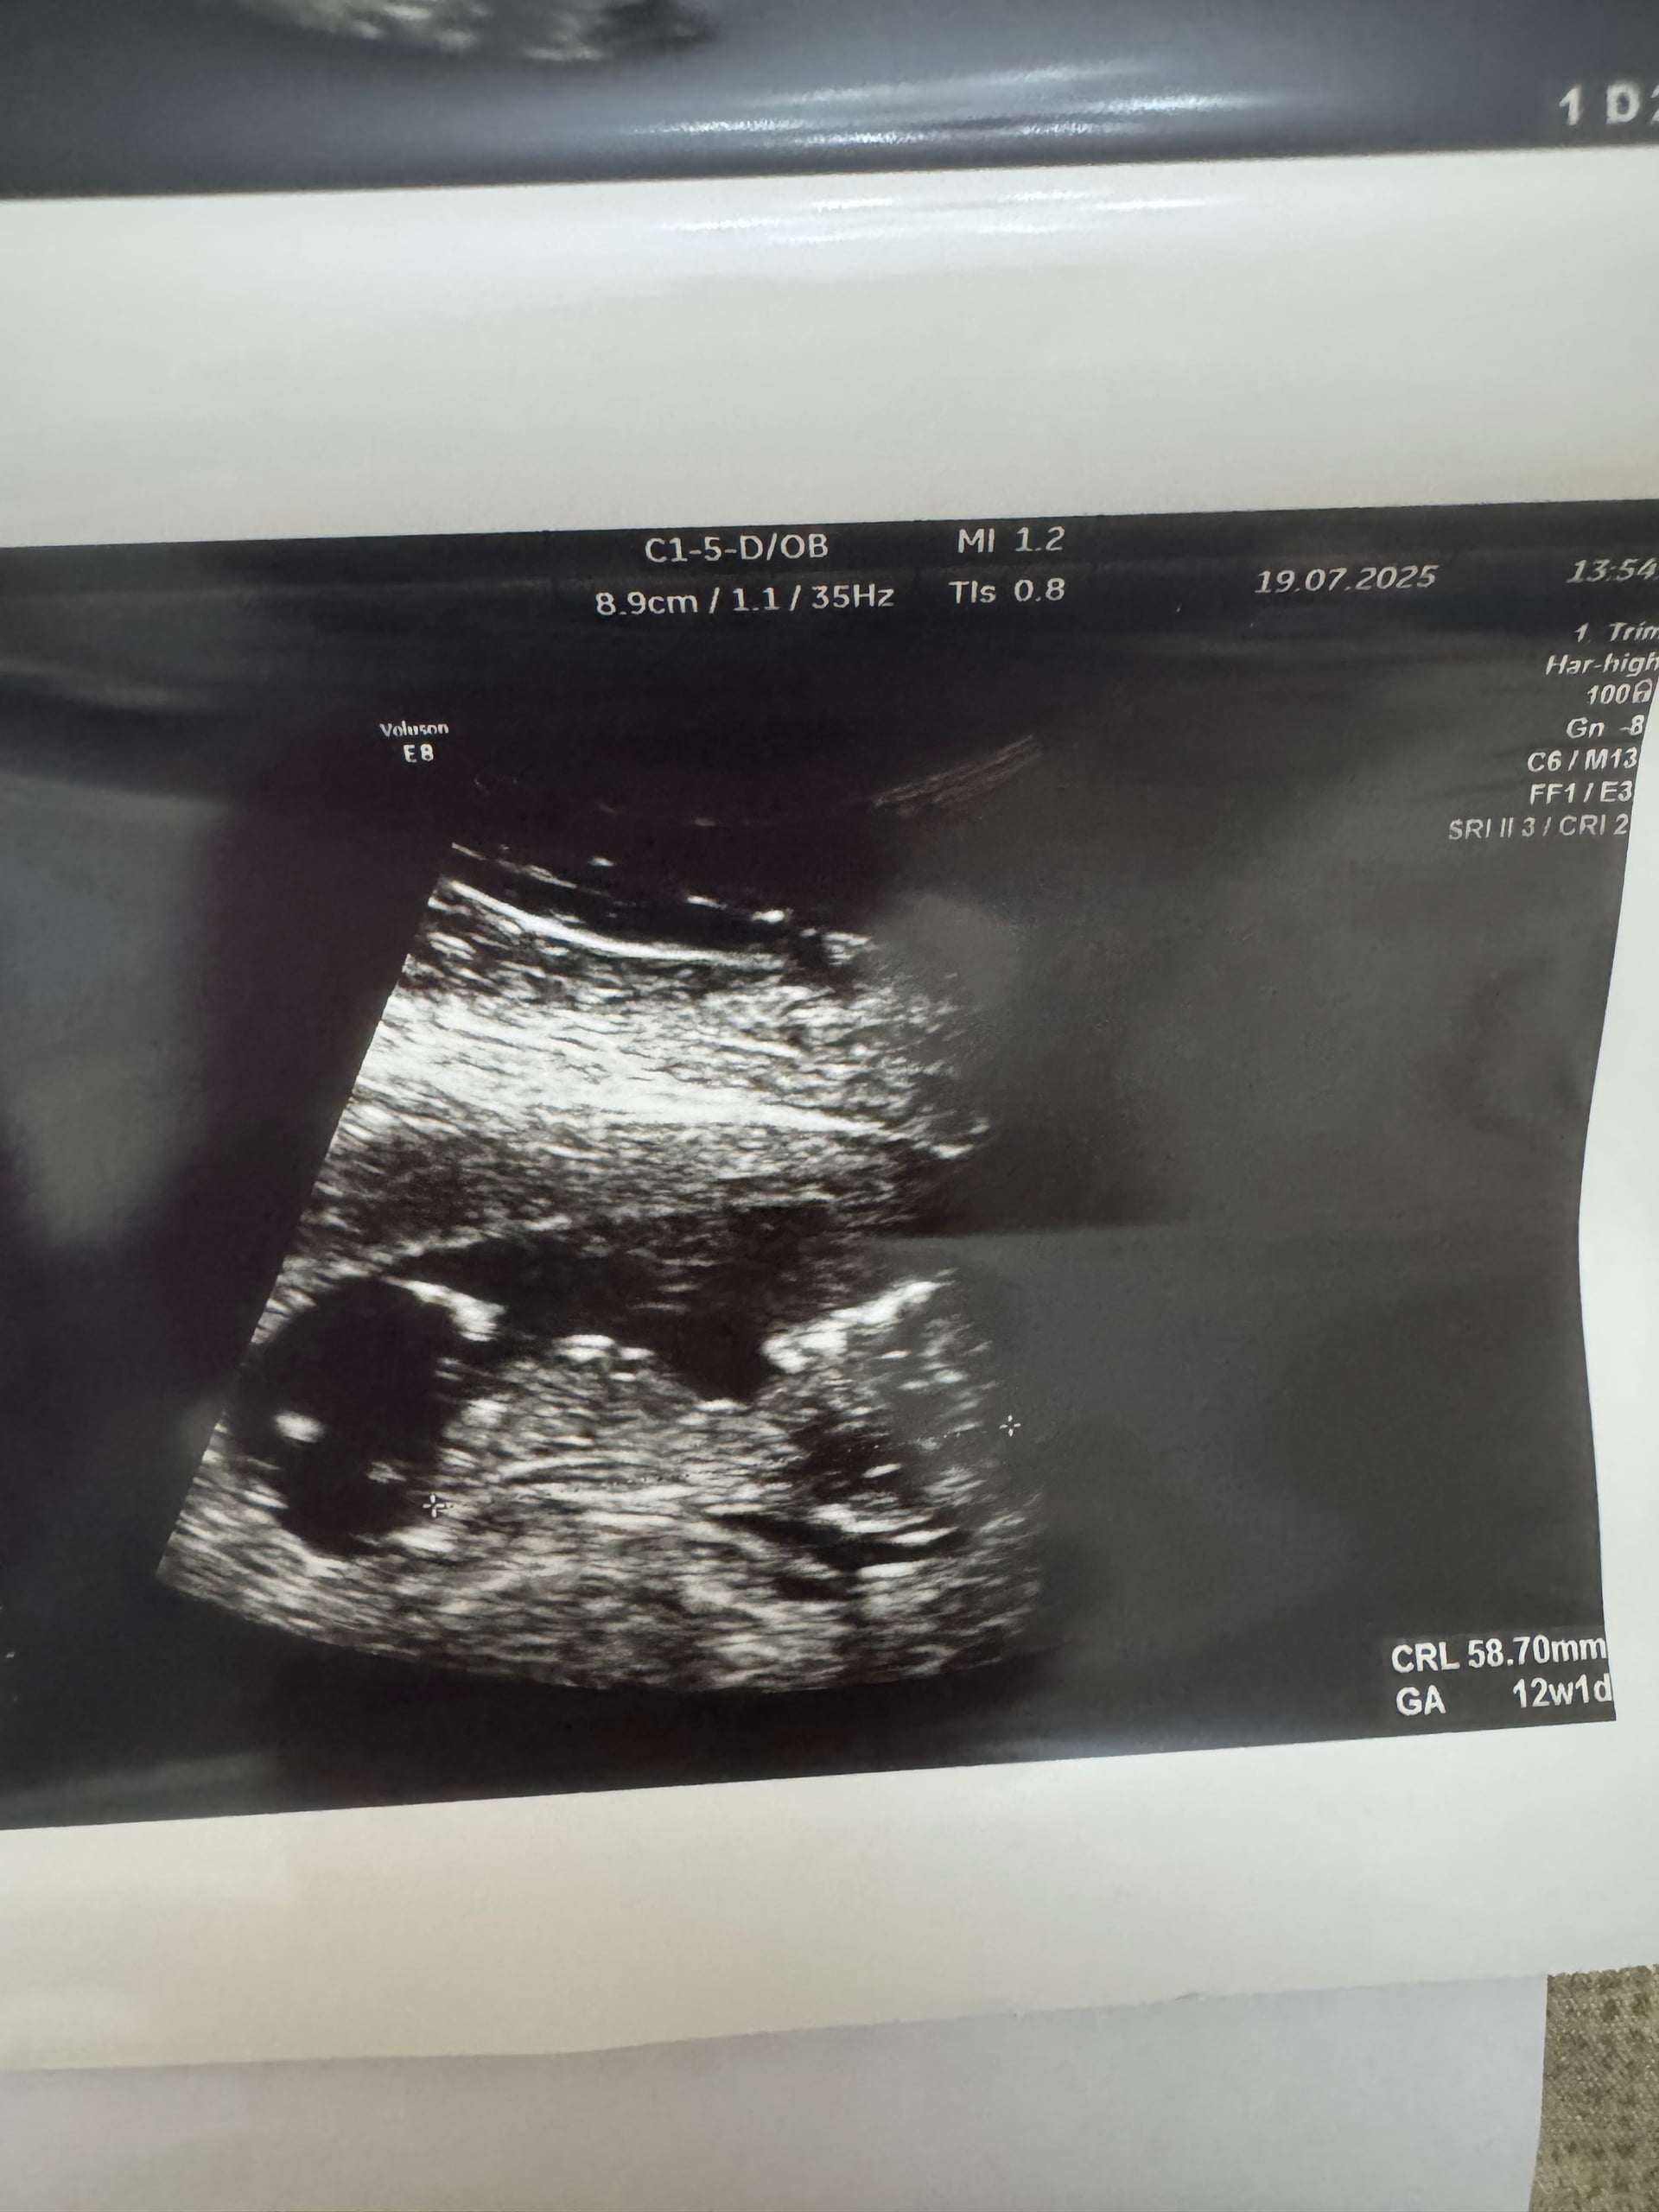

He can 12 heftelikdi

Allah saxlasın bacı. Sağ salamat qucağıva al İnşAllah. Tam bilinmir kisə ama məncə oğlandı